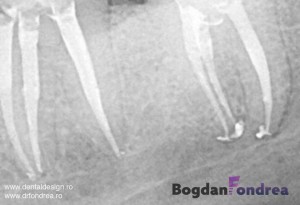

Radiografia de control dupa tratamentul de canal

Atunci cand in practica stomatologica se impune realizarea unui tratament de canal, fie ca este...

Cum se realizeaza un tratament de canal?

Tratamentul de canal sau "scoaterea nervului" se efectueaza atunci cand pulpa dintelui este afectata ireversibil,...